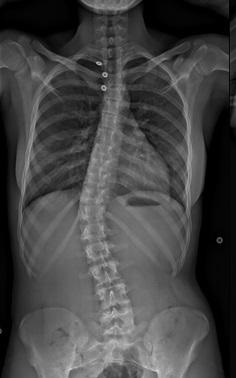

Les troubles statiques de la colonne vertébrale chez l'enfant sont principalement représentés par des scolioses, des cyphoses ou des anomalies de charnière lombosacrée (spondylolyse et spondylolisthésis). Ils nécessiteront toujours une radiographie d'ensemble du rachis. Leur suivi doit être régulier.